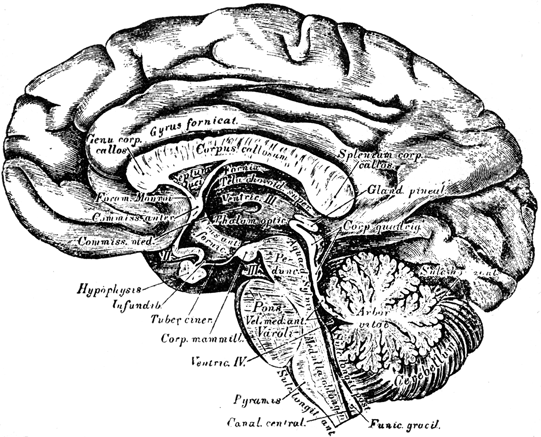

Anatomy of the Brain.—Anatomy is considered the driest

and most difficult of biological studies, but a careful attention to our

description of the brain will show that it is very intelligible. After

we get through with the anatomy, the description of organs and

their functions is simple and practical. Every one should understand

the outlines of cerebral anatomy, and then he can discuss the subject

Chapter II—Structure of the Brain.

Man a triple being—Materialists and illusionists misconceive him—Relation

of the soul to the brain and body—The nervous system;

illustration—Embryonic condition—Anatomical descriptions unsatisfactory

and the phrenological school incorrect—Exterior view

of the brain in the head, illustrated and described—The cerebrum,

cerebellum, and tentorium—Interior view of the base of the skull—Bones

of the head illustrated—Division of the brain into lobes

and convolutions, with illustration—Frontal, middle, parietal,

tempero-sphenoidal, and occipital—Anatomical plan or grouping of

convolutions differs from their actual appearance—View of the superior

surface illustrated—Difference between the irregular convolutions

and the angular maps—View of the inferior surface of the

brain—Illustration and description of the parts—Interior view of

section on the median line—Divided and undivided surfaces-Corpus

callosum explained—The two brains and their diagonal

relations to the body—Penetrating and describing the lateral

ventricles—The serum in the brain—Variations of serum and

blood—Variations in hydrocephalus and insanity—Our power to

modify the brain and change our destiny—Power of education—Responsibility

of society—The lateral ventricles the centre of the

brain—Base of the ventricles, the great inferior ganglia of the

brain, corpora striata, and thalami—Their radiating fibres inclosing

a cavity—The thalami and their commissure and third ventricle—The

medulla oblongata, cerebellum, and arbor vitæ—The pons

Varolii and crura of the brain—the corpora quadrigemina, pineal

gland, fourth ventricle, and calamus scriptorius.

Let us take an exterior view by

removing one half of the skull from

the right side of the head. This

enables us to see that the front

portion of the brain rests above the

sockets of the eyes, coming down in

the centre as low as the root of the

nose, but a little higher exteriorly.

When we touch the forehead just